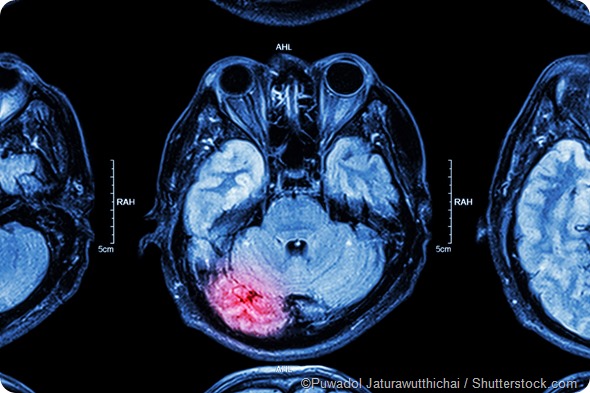

Human brain plasticity has mostly been studied using non-invasive imaging methods, because these techniques allow us to measure the gray matter (neurons), white matter (axons) at a somewhat coarse level. MRI and fMRI techniques provide snapshots and video of the brain in function, and that allows us to capture changes in the brain that are interpreted as plasticity.